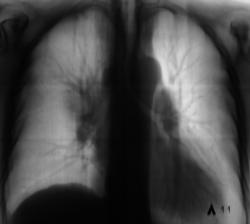

После взятия поциента "на контроль" произведи стандартное дообследование. Пациент жалоб не предъявляет, обращает внимание на небольшую одышку и "сухой" непродуктивный кашель. Произведено стандартное дообследование.

деформация правого корня. Он смещён немного вверх. Картина похоже на течение онкопроцесса.

Новообразование в области правого верхнедолевого бронха, центральная форма, ателектаз или обструктивный пневмонит в третьем сегменте, лимфангит во всей доле, расширение вехнего средостения вправо - метастазы?

Валентин Львович, а Вы не хотите сделать боковую томограмму через тень (корень) и томограмму на правый в/долевой бронх. Потому как ни одной из томограмм ни тень, ни бронхи справа не в срезе, а есть у меня такое впечатление, что имеет место периферический узел в S3, проекционно накладывающийся на тень корня, кроме того, при таком конгломерате в корне, должна быть более выражена гиповентиляция...